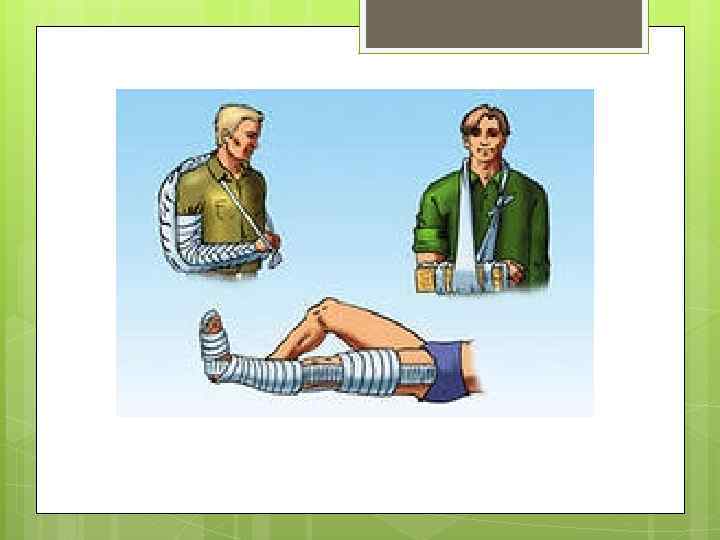

Накладывайте шину на кость так, чтобы она перекрывала суставы выше и ниже места травмы Накладывая шину на сустав, захватывайте сустав выше и ниже места травмы Если возможно, накладывайте шину с обеих сторон поврежденной конечности, чтобы она не двигалась Шина может быть сделана из любых материалов, которые окажутся (а точнее не окажутся) под рукой. Например, палка, ветка, картон, доска, лыжа и т. д. Телошина: в данном случае используется неповрежденная част тела, например, сломанный палец привязывается к соседнему, сломанная нога — к здоровой. Не пытайтесь вправить сустав или сломанную кость на место!

Накладывайте шину на кость так, чтобы она перекрывала суставы выше и ниже места травмы Накладывая шину на сустав, захватывайте сустав выше и ниже места травмы Если возможно, накладывайте шину с обеих сторон поврежденной конечности, чтобы она не двигалась Шина может быть сделана из любых материалов, которые окажутся (а точнее не окажутся) под рукой. Например, палка, ветка, картон, доска, лыжа и т. д. Телошина: в данном случае используется неповрежденная част тела, например, сломанный палец привязывается к соседнему, сломанная нога — к здоровой. Не пытайтесь вправить сустав или сломанную кость на место!

Как наложить шину на плечо? Осторожно разместить сломанную руку сбоку, предплечье — под прямым углом поперек грудной клетки. Шину наложить с внешней стороны руки. Завяжите на шее перевязь для поддержания руки.

Как наложить шину на плечо? Осторожно разместить сломанную руку сбоку, предплечье — под прямым углом поперек грудной клетки. Шину наложить с внешней стороны руки. Завяжите на шее перевязь для поддержания руки.